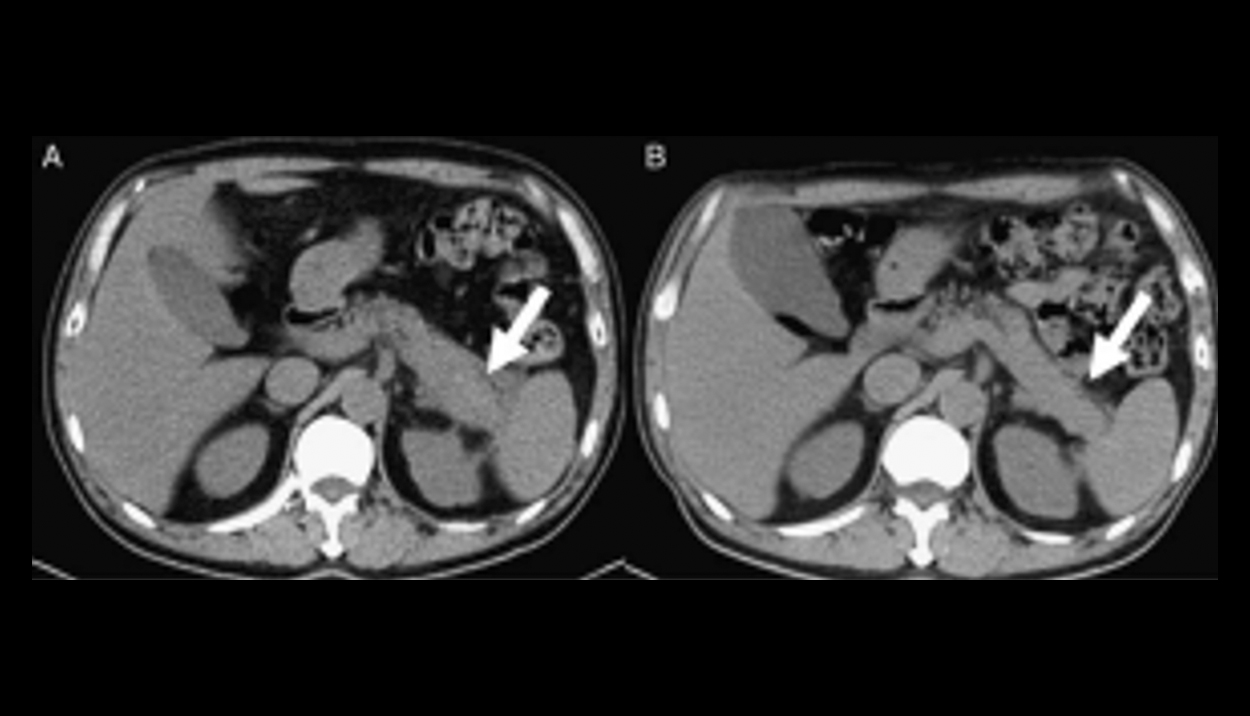

Focal Autoimmune Pancreatitis Mimicking Pancreatic Cancer on FDG PET/CT Imaging

Abstract:Autoimmune pan creat it i generally results in diffuse increased FDG atiytiougoutthepinTes on PET CT age.We peta cse of focal autoimmune pancreatitis with abn oral FDG activity involving only the pancreatic a il on PET/CTina6l-year-oldman who was pro vii on ally diag-nosedas having pancreatic cancer based on the CT find ngs.The diagnosis of au lo immune pan crea ii was based on pathological exam in at on and clev a led serumimmunogo-bunG4kvl. Following the steroid the npy,the paintwasgradually recovered.Key Words:cancer, FDG,PET/CT, type l autoimmune pane re at it is (Clin Nucl Med 2018; 43:57-59)